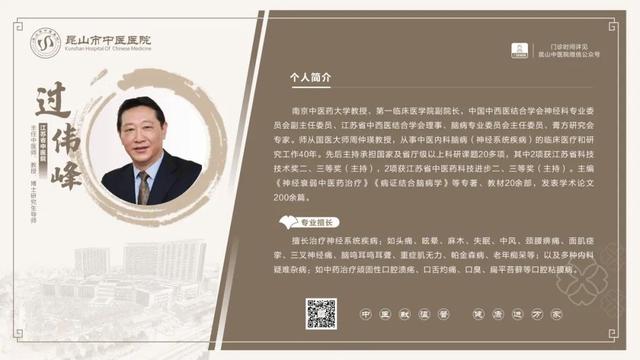

6��23��-6��29��������ר�ҳ���һ����

6��23��-6��29�������dz���ר�ҽ���